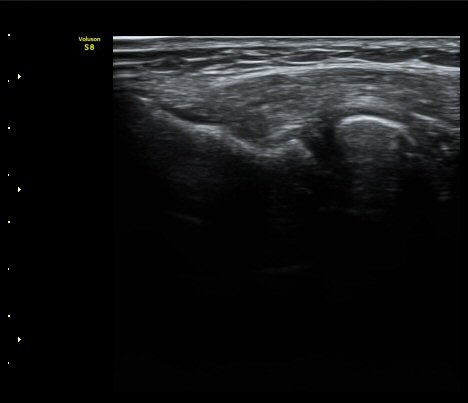

ÃÊÀ½ÆÄ °Ë»ç